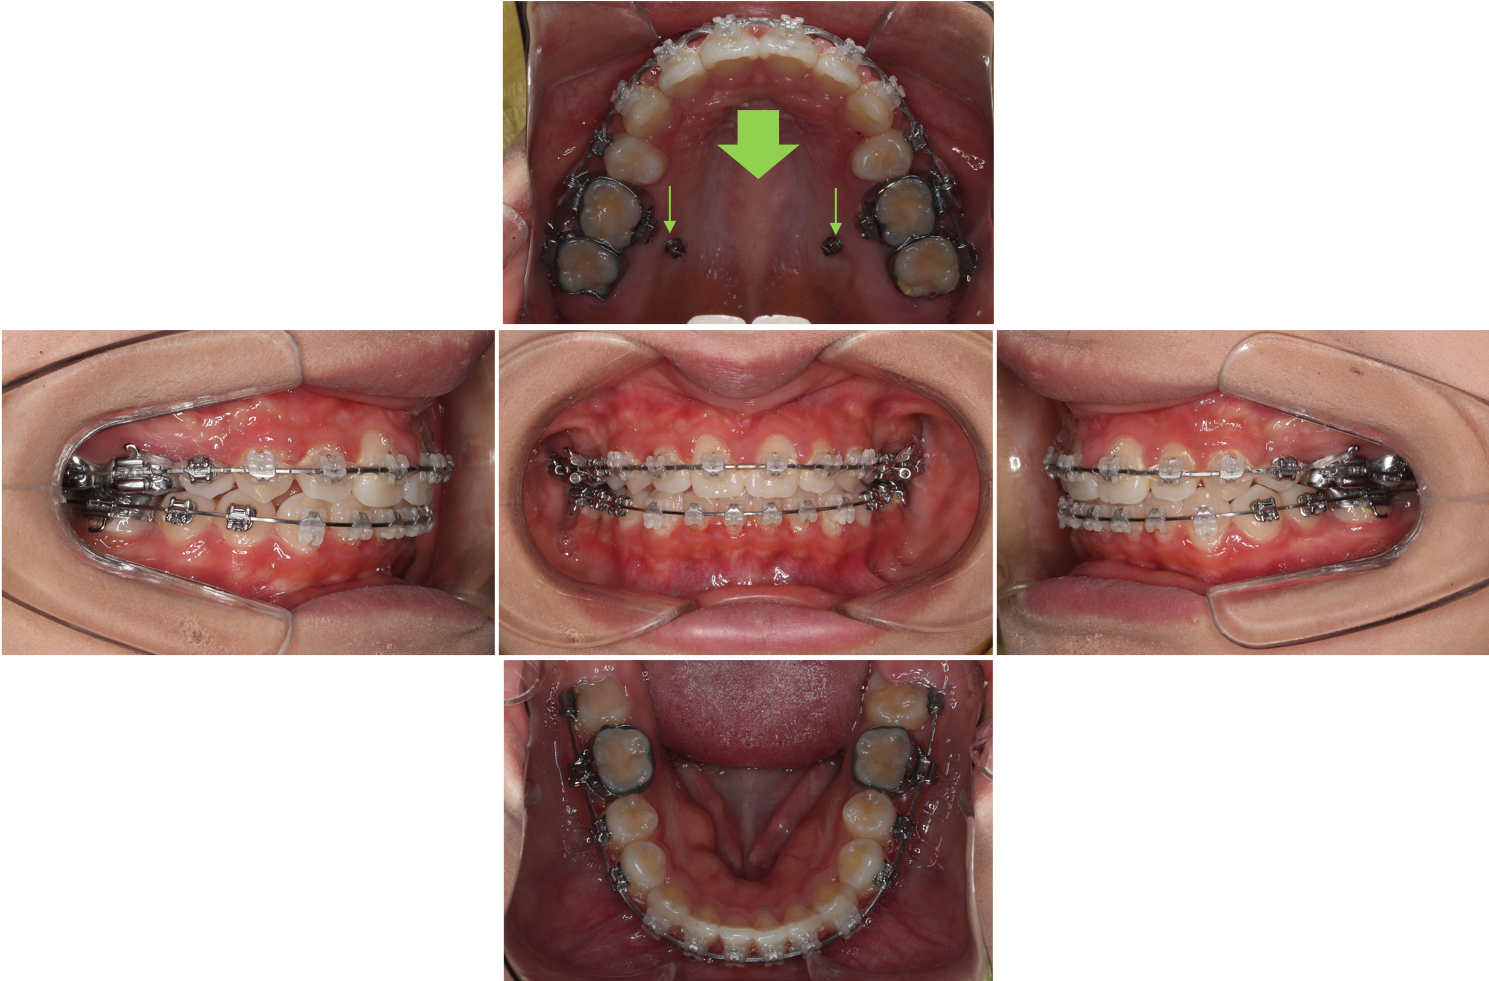

治療中

本症例は上顎前歯の後方移動量が最大限必要であったため口蓋側壁に植立した歯科矯正用アンカースクリューを使用して、上顎前歯の後方移動(上顎左右第一小臼歯抜歯)を行いました。